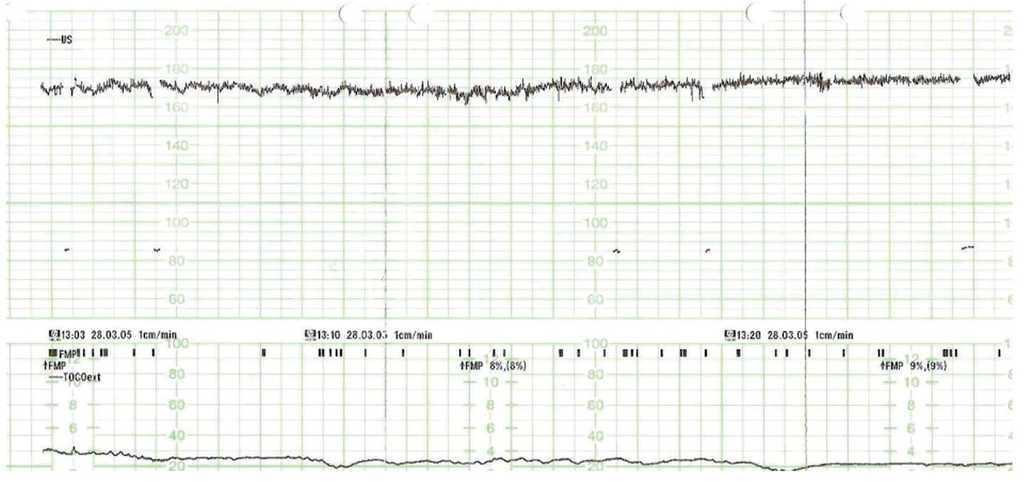

Figura 1.Registro cardiotocográfico: destaca la taquicardia fetal con disminución de la variabilidad.

Figura 2.Registro cardiotocográfico: destaca la taquicardia fetal con disminución de la variabilidad.

Paciente secundigesta, caucásica, de 35 años, extranjera, de visita en nuestro país. Como antecedentes personales presentaba un cuadro de asma desde la infancia-adolescencia que requería tratamiento con betamiméticos inhalados y por el cual no había necesitado asistencia en urgencias en ningún momento de su vida. De sus antecedentes familiares destacaba: su madre, asmática, había tenido diversos episodios de broncospasmo grave, que habían requerido ingreso hospitalario, y había tenido un parto normal anterior, con un hijo que vivía sano. En la semana 32 de gestación comenzó con un episodio progresivo de tos y expectoración mucoverdosa, que desembocó en un cuadro de broncospasmo importante, por el cual es derivada a nuestro centro. A su ingreso, la paciente mostraba un buen estado general; estaba consciente y orientada, normocoloreada y normohidratada. Como constantes vitales presentaba: presión arterial (PA) 120/60 mmHg; frecuencia cardíaca (FC) de 80 latidos/min; frecuencia respiratoria (FR) de 25 respiraciones/min y temperatura de 37 °C. A la auscultación de los campos pulmonares se identificaban sibilancias múltiples generalizadas por ambos campos, con murmullo vesicular conservado. En la exploración obstétrica presentaba un cérvix uterino sin modificaciones, una altura uterina de 32 cm y unos tonos fetales normales. En la ecografía obstétrica se evidenció un feto vivo en situación longitudinal y presentación cefálica, somatometría correspondiente con amenorrea, placenta normoinserta, tipo I de la clasificación de Grannum, e índice de líquido amniótico medido con la técnica de Phelam de 13 cm. El registro cardiotocográfico a su ingreso fue normal, con un feto reactivo y adinamia uterina. Durante su estancia en urgencias inició un empeoramiento progresivo del estado general con aumento de la disnea, que precisó de tratamiento enérgico con metilprednisona por vía intravenosa, betamiméticos inhalados, betamiméticos por vía subcutánea, adrenalina por vía subcutánea y oxigenoterapia. Pese al tratamiento instaurado, continuó el empeoramiento franco del estado general; la paciente se encontraba taquicárdica, taquipneica, con intensa depresión inspiratoria, dificultad para la pronunciación de monosílabos y cianosis perilabial. Presentó además: PA 150/95 mmHg, FC 150 latidos/min, FR 44 respiraciones/min y pulso paradójico con descenso de más de 15 mmHg de PA sistólica con la inspiración. En la auscultación pulmonar continuaban las múltiples sibilancias en ambos campos pulmonares. Con el diagnóstico de cuadro de asma grave con criterios de estatus asmático, se derivó a la paciente a la unidad de medicina intensiva de nuestro complejo hospitalario. En esa unidad fue imperiosa la necesidad de intubación orotraqueal y el inicio de ventilación mecánica por la situación de estatus asmático. En los subsiguientes días la paciente permaneció muy inestable, con cuadros de desaturación de la fracción de oxígeno hasta un 70-80%, con intolerancia al estímulo externo y a la movilización, con ventilación a alta frecuencia tras la producción de enfisemas subcutáneos, por lo que permanecía sedada con dosis altas de propofol y midazolam. Los registros fetales pasaron a ser taquicárdicos, no reactivos y no desacelerativos (figs. 1 y 2). Estos registros se correlacionaron con la medicación que recibía la paciente. Tras 7-8 días de inestabilidad, se inició una ligera tendencia a la estabilidad y, dado el menor riesgo materno tras la mejoría, se decidió la extracción fetal, con la finalidad de mejorar la función respiratoria materna y evitar posibles efectos en el bienestar fetal. En semana 33 + 5 días se realizó una cesárea tipo Pfannestiel, sin incidencias. Nació un feto de 2.450 g de peso, con una puntuación en la prueba de Apgar de 5/9 y buena adaptación cardiorrespiratoria a la vida neonatal. En el postoperatorio, la paciente inició una importante mejoría; se normalizaron la FC, la FR y el porcentaje de saturación de oxígeno, por lo que requirió dosis menores de sedación y menor frecuencia de ventilación asistida, y pudo extubarse 48 h tras la cesárea. Desde el momento de la extubación se produjo una mejoría total hasta la restauración del estado general de la paciente ad íntegrum.